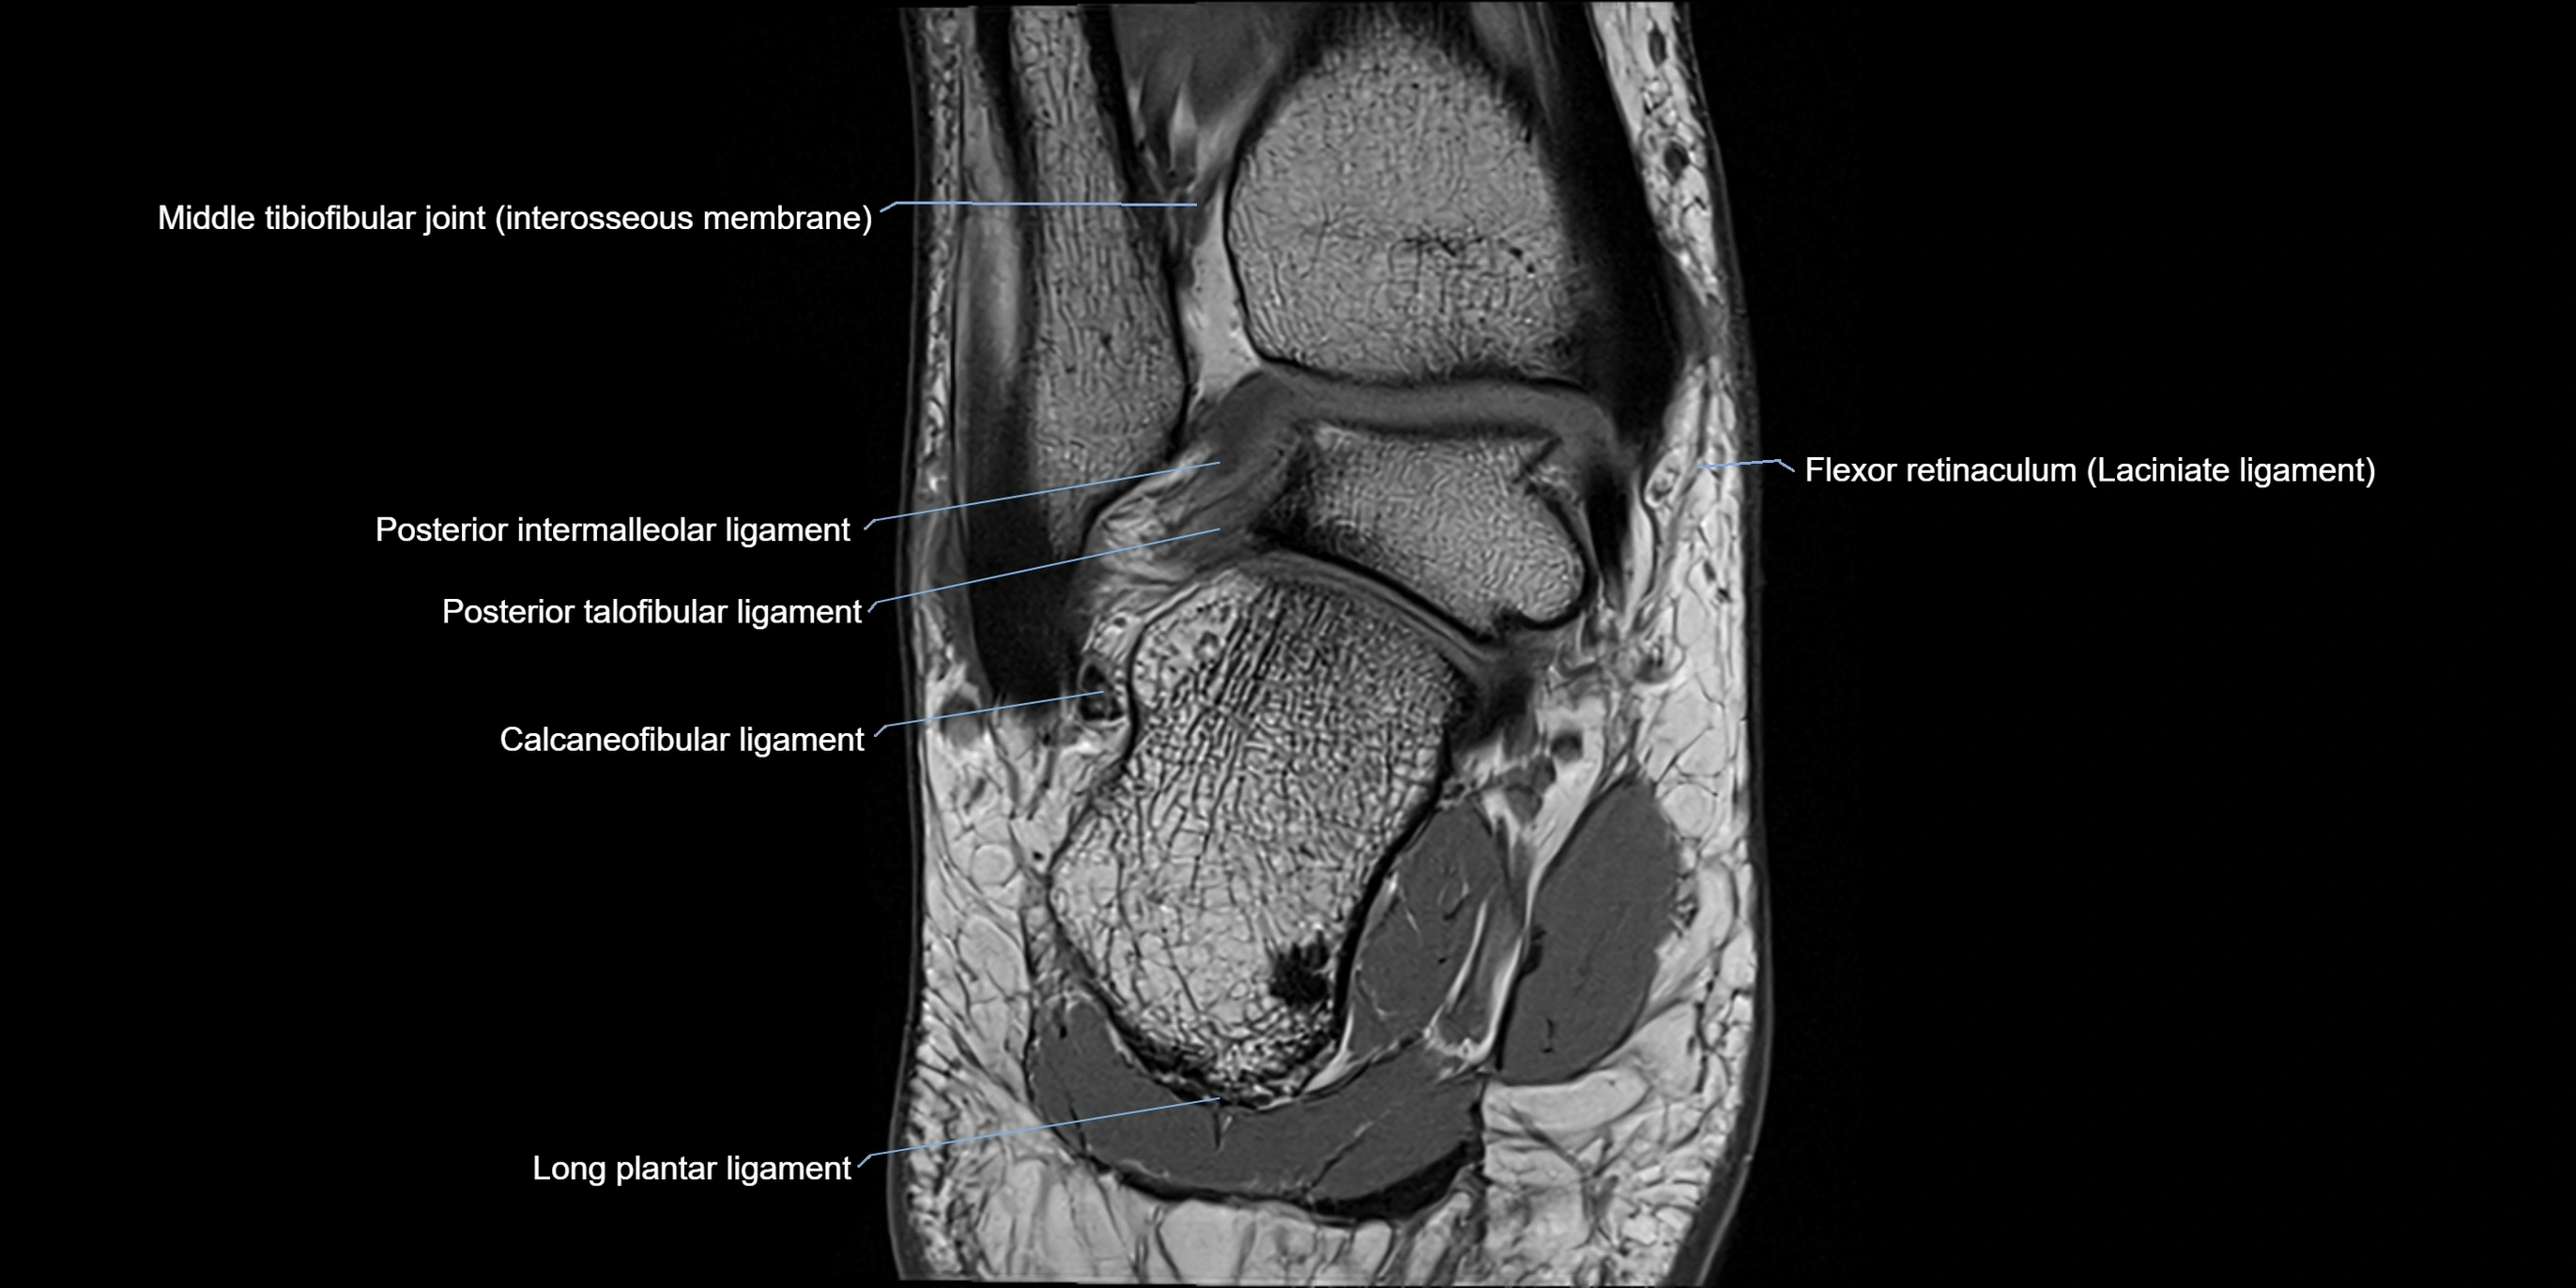

MRI image

image